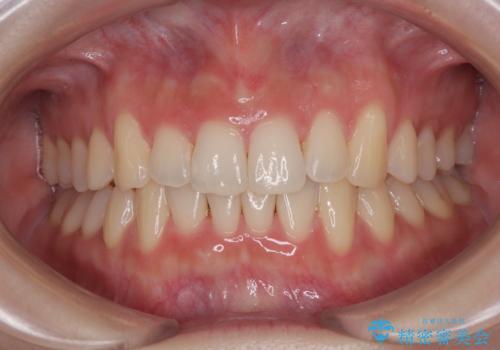

受け口と八重歯を改善 インビザライン矯正治療